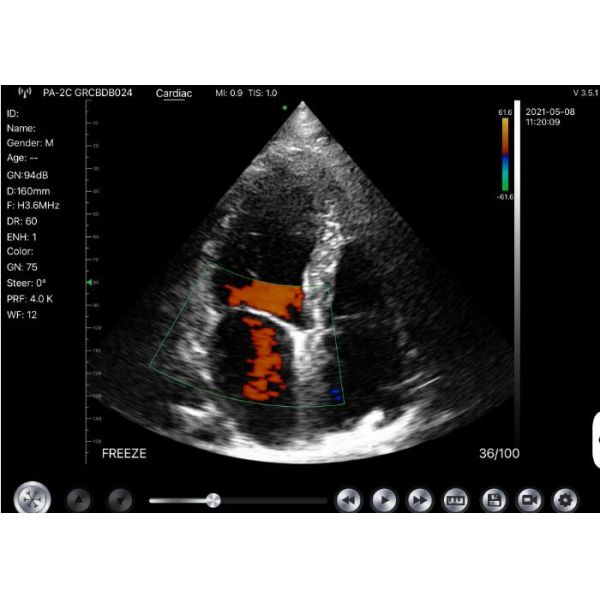

Images

|

|

Windows Pocket Ultrasound Scanner Machines Electronic Phased Array Images |